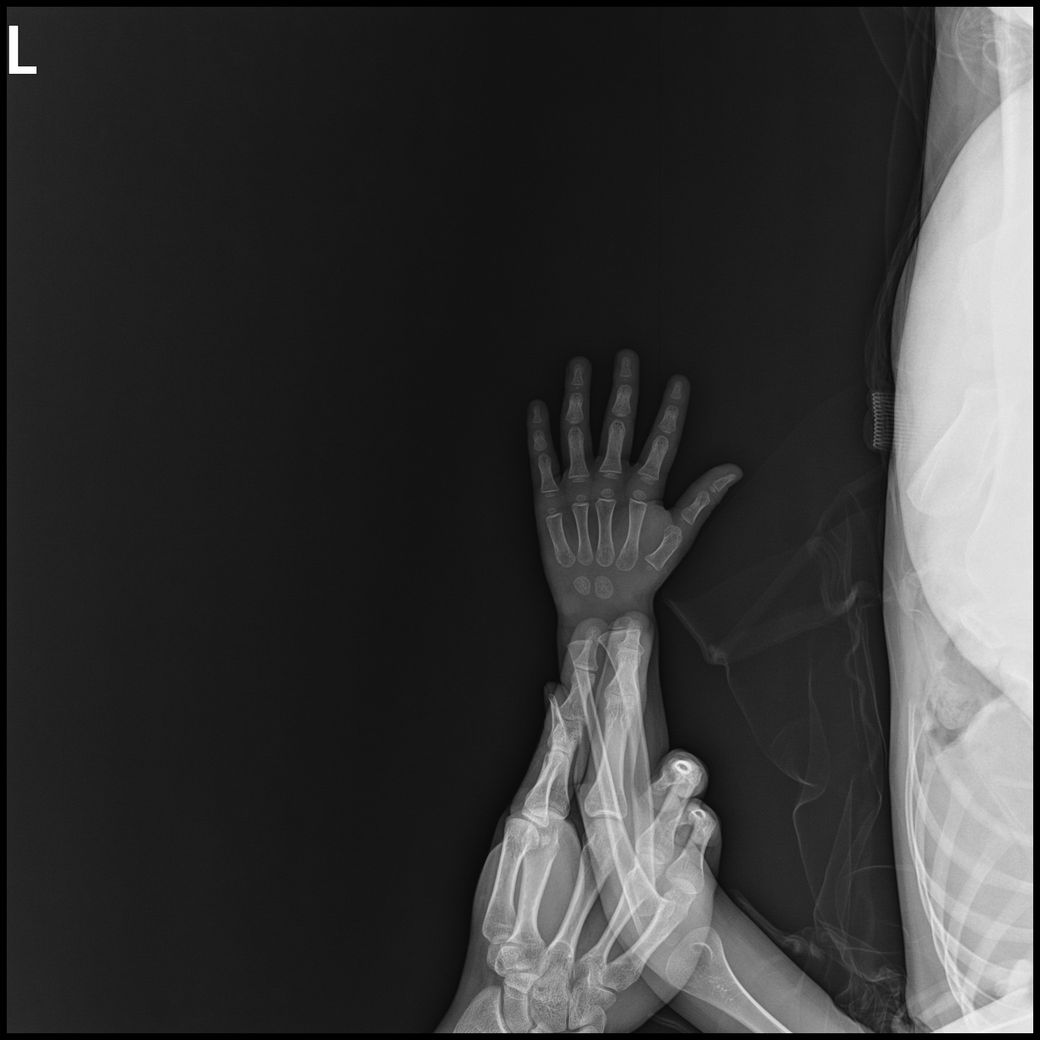

아기 손발 엑스레이를 찍게되었는데요.

손목, 발목까지 6-8장 찍기로 안내받았으나,

고관절,복부일부,생식기등 민감부위등이 추가로 촬영되었고

발도 다리가 다 찍혔고 총 19장이 찍혔습니다.

- 몸통일부+손같이찍힘 : 6장

- 손부터 팔꿈치까지 : 3장

- 발~다리사진 : 10장

• 1번 째 사진